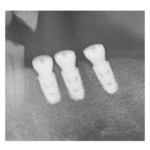

治療途中のインプラント症例

治療途中のインプラント症例です。 主訴 しっかり噛めるようにしたい 年齢 60歳 ...